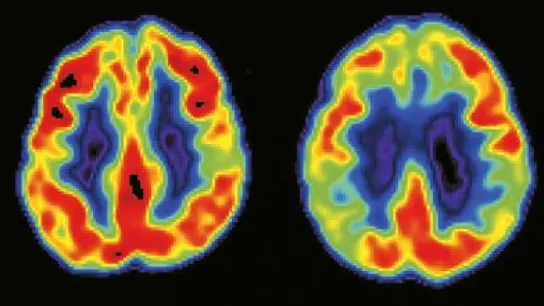

Un equipo liderado por el Consejo Superior de Investigaciones Científicas, CSIC, ha descubierto una estimulación cerebral profunda que consiste en implantar unos electrodos en la corteza subcingulada y aplicar una corriente eléctrica. Dicha terapia se utiliza con éxito en enfermos con depresión que se muestran resistentes al tratamiento farmacológico con antidepresivos.

El CSIC, ha descubierto en ratas que cuando se aplica dicha terapia en la corteza infralímbica se produce una liberación del glutamato, principal transmisor excitador del cerebro, en la corteza cerebral y activa el receptor AMPA, lo que produce la acción antidepresiva. El trabajo se ha publicado en la revista Cerebral Cortex.